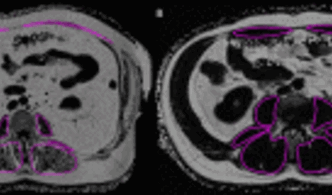

CT- und MR-Bildgebungsparameter zur Körperzusammensetzung wie Muskeldichte, Muskelfettanteil (Abbildung 8), Muskelfläche oder Körperfettverteilung stehen Berichten zufolge in Zusammenhang mit Skelettmuskelschwund (z. B. Sarkopenie), Gebrechlichkeit, Krebs, Osteoarthritis und Stoffwechselkrankheiten, einschließlich Diabetes und metabolischem Syndrom. In diesem Zusammenhang können Längsschnittstudien dazu beitragen, die Auswirkungen der Körperzusammensetzung auf die Pathogenese und das Fortschreiten von Krankheiten besser zu verstehen. Darüber hinaus können Analysen der verschiedenen abdominalen Körperkompartimente (subkutanes Fett, viszerales Fett, Bauchmuskeln; Abbildung 9) zur Risikostratifizierung, zur Einleitung von Präventivmaßnahmen und zur Nachbeobachtung während und nach therapeutischen Eingriffen beitragen.